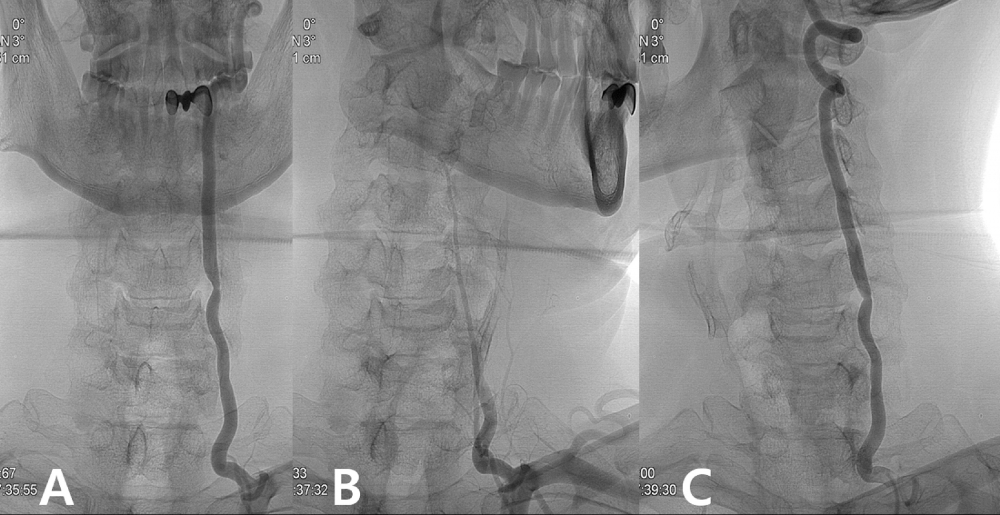

(A) Dynamic angiography shows narrowing of the left vertebral artery at the C5-6 level.

(B) The patient was positioned with his head turned 45° to the left; blood flow through the left vertebral artery was nearly completely blocked.

(C) When the patient's head was turned to the right, blood flow through the left vertebral artery was normal.

From: Lee CS, Lee HY, Yang TK. Rotational vertebral artery occlusion syndrome: misnomers and classification. Clin Neurol Neurosurg. 2015;131:18-20. doi:10.1016/j.clineuro.2015.01.016